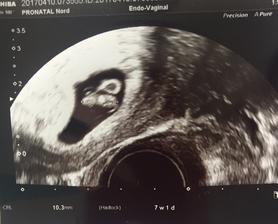

@dagmarka13 ahojky zitra me ceka prvni uktrazvuk. Ted jsem delala jeste jeden kontrolni test jestli neslabne a ok. Zaludek zlobi, bricho obcas da o sobe vedet tak beru na doporuceni dr magnesium a taky lehke spineni, ale to by melo byt v tom 6tt v poradku. To vis strach mam, ale uz se chci radovat ❤️🤰🏻

@verryk dekuji moc. Dnes byla kontrola a vse v poradku. Mi i je o 3 dny napred tedy 11+0 a mela sem byt 11+4